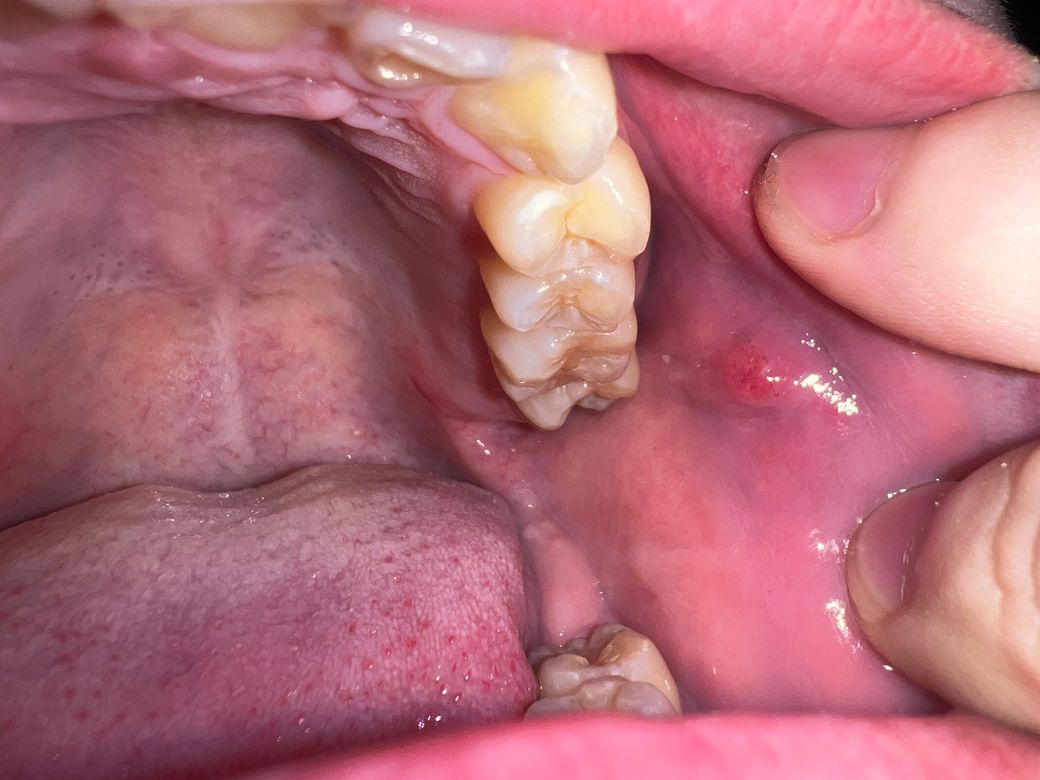

오늘 밥을 먹다가 볼 점막에 혹 처럼 만져지는 게 있어서 사진을 찍었습니다. 사진에서는 잘 안 보이지만 원래 점막을 찢고 나온 거 처럼 아래에 하얀 점막이 보이고 툭 올라온 것에는 붉고 작은 반점이 보입니다 그리고 혀로 건드려도 아프지 않고 딱딱한 게 느껴집니다

Stensen duct로 보여집니다.

걱정은 안하셔도 되겠고 침이 나오는 곳이라고 생각하시면 되겠습니다.

사진상 구내염으로 보이며, 충분한 휴식과 영양섭취를 권합니다. 염증이 덧나지 않도록 소독용 가글인 헥사메딘 가글액으로 가글을 하여 관리하고, 만약 2주이상 사라지지 않는 경우에는 치과 진료를 권합니다.